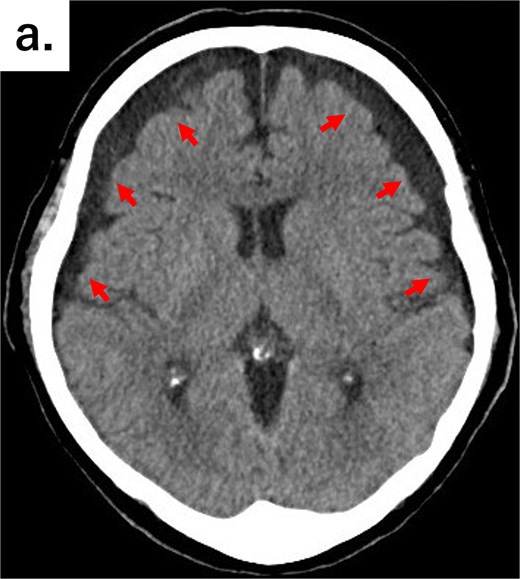

An 82-year-old man visited the emergency department with a chief complaint of slurred speech. There were no digestive symptoms, such as diarrhea, malabsorption, bloating, chronic abdominal pain, or internal bleeding. His respiratory and circulatory dynamics were stable, and the blood test results were as follows: White blood cell (WBC) 12 200/mm3, Hgb 11.3 g/dl, blood urea nitrogen (BUN) 27.4 mg/dl, Cre 1.65 mg/dl, C-reactive protein (CRP) 7.79 mg/dl, no abnormalities in liver function, and no biliary system elevations. Computed tomography (CT) revealed chronic bilateral subdural hematomas (Fig. 1). Normal neck-to-pelvis CT revealed mild bilateral pneumonia (Fig. 2a). Moreover, multiple diverticula were found, primarily in the upper small intestine. Two abscesses showing increased density of the surrounding fatty tissue were identified: one was a 5-cm abscess in the mesentery of the small intestine and the other had air in the mesentery on the distal side (Fig. 2b and c). As there were no obvious signs of perforation and the patient's vitals were stable, conservative treatment was also an option, but the formation of a 5-cm abscess within the mesentery was a difficult location to puncture under CT guidance; therefore, we opted for emergency surgical treatment.

Axial CT image of the head showing bilateral chronic subdural hematomas (arrows).